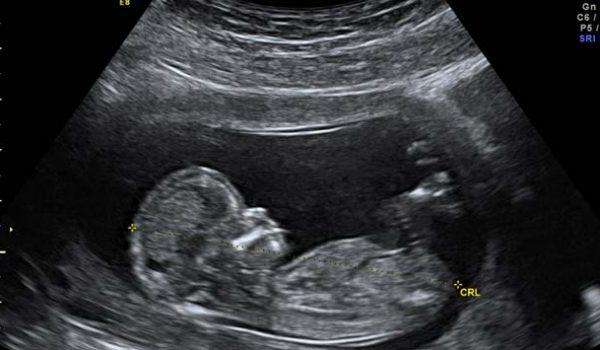

Ultrassonografia Geral

A ultrassonografia é um método alicerçado no fenômeno de interação de som e tecidos. A partir da transmissão de onda sonora de alta frequência observamos as propriedades mecânicas dos tecidos. Saiba Mais…